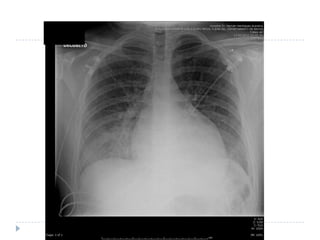

FC 146x

PA 95/52 Tax 36,4 Sat 95%

Yugulares Planas

RR2T sin soplos

MP (+) Simétrico sin ruidos agregados

Motivo de Consulta  Eldía de la consulta en la mañana comienza con dificultad respiratoria y palpitaciones rápidas persistentes. Angor (-) Síncope (-) Sensación Febril (-)  Examen:      FC 146x PA 95/52 Tax 36,4 Sat 95% Yugulares Planas RR2T sin soplos MP (+) Simétrico sin ruidos agregados